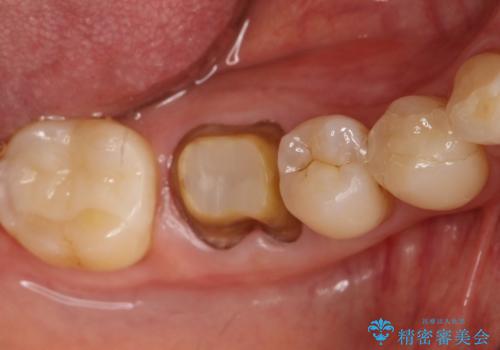

咬んだ時の違和感 顕微鏡で発見された歯の穴を処置し、かみ合わせを回復する

- 再根管治療にて発見されたパーフォレーションを修復し、改めてかぶせ物を製作する。

レントゲンに大きな問題がなくても、実際に顕微鏡で見ることにより様々な問題が露呈することはよくあります。

再治療の繰り返しにより歯に穴があいてしまっていることもよくありますが、このような深い位置の穴は、特殊なセメントで封鎖することにより非常に経過良く処置することができます。